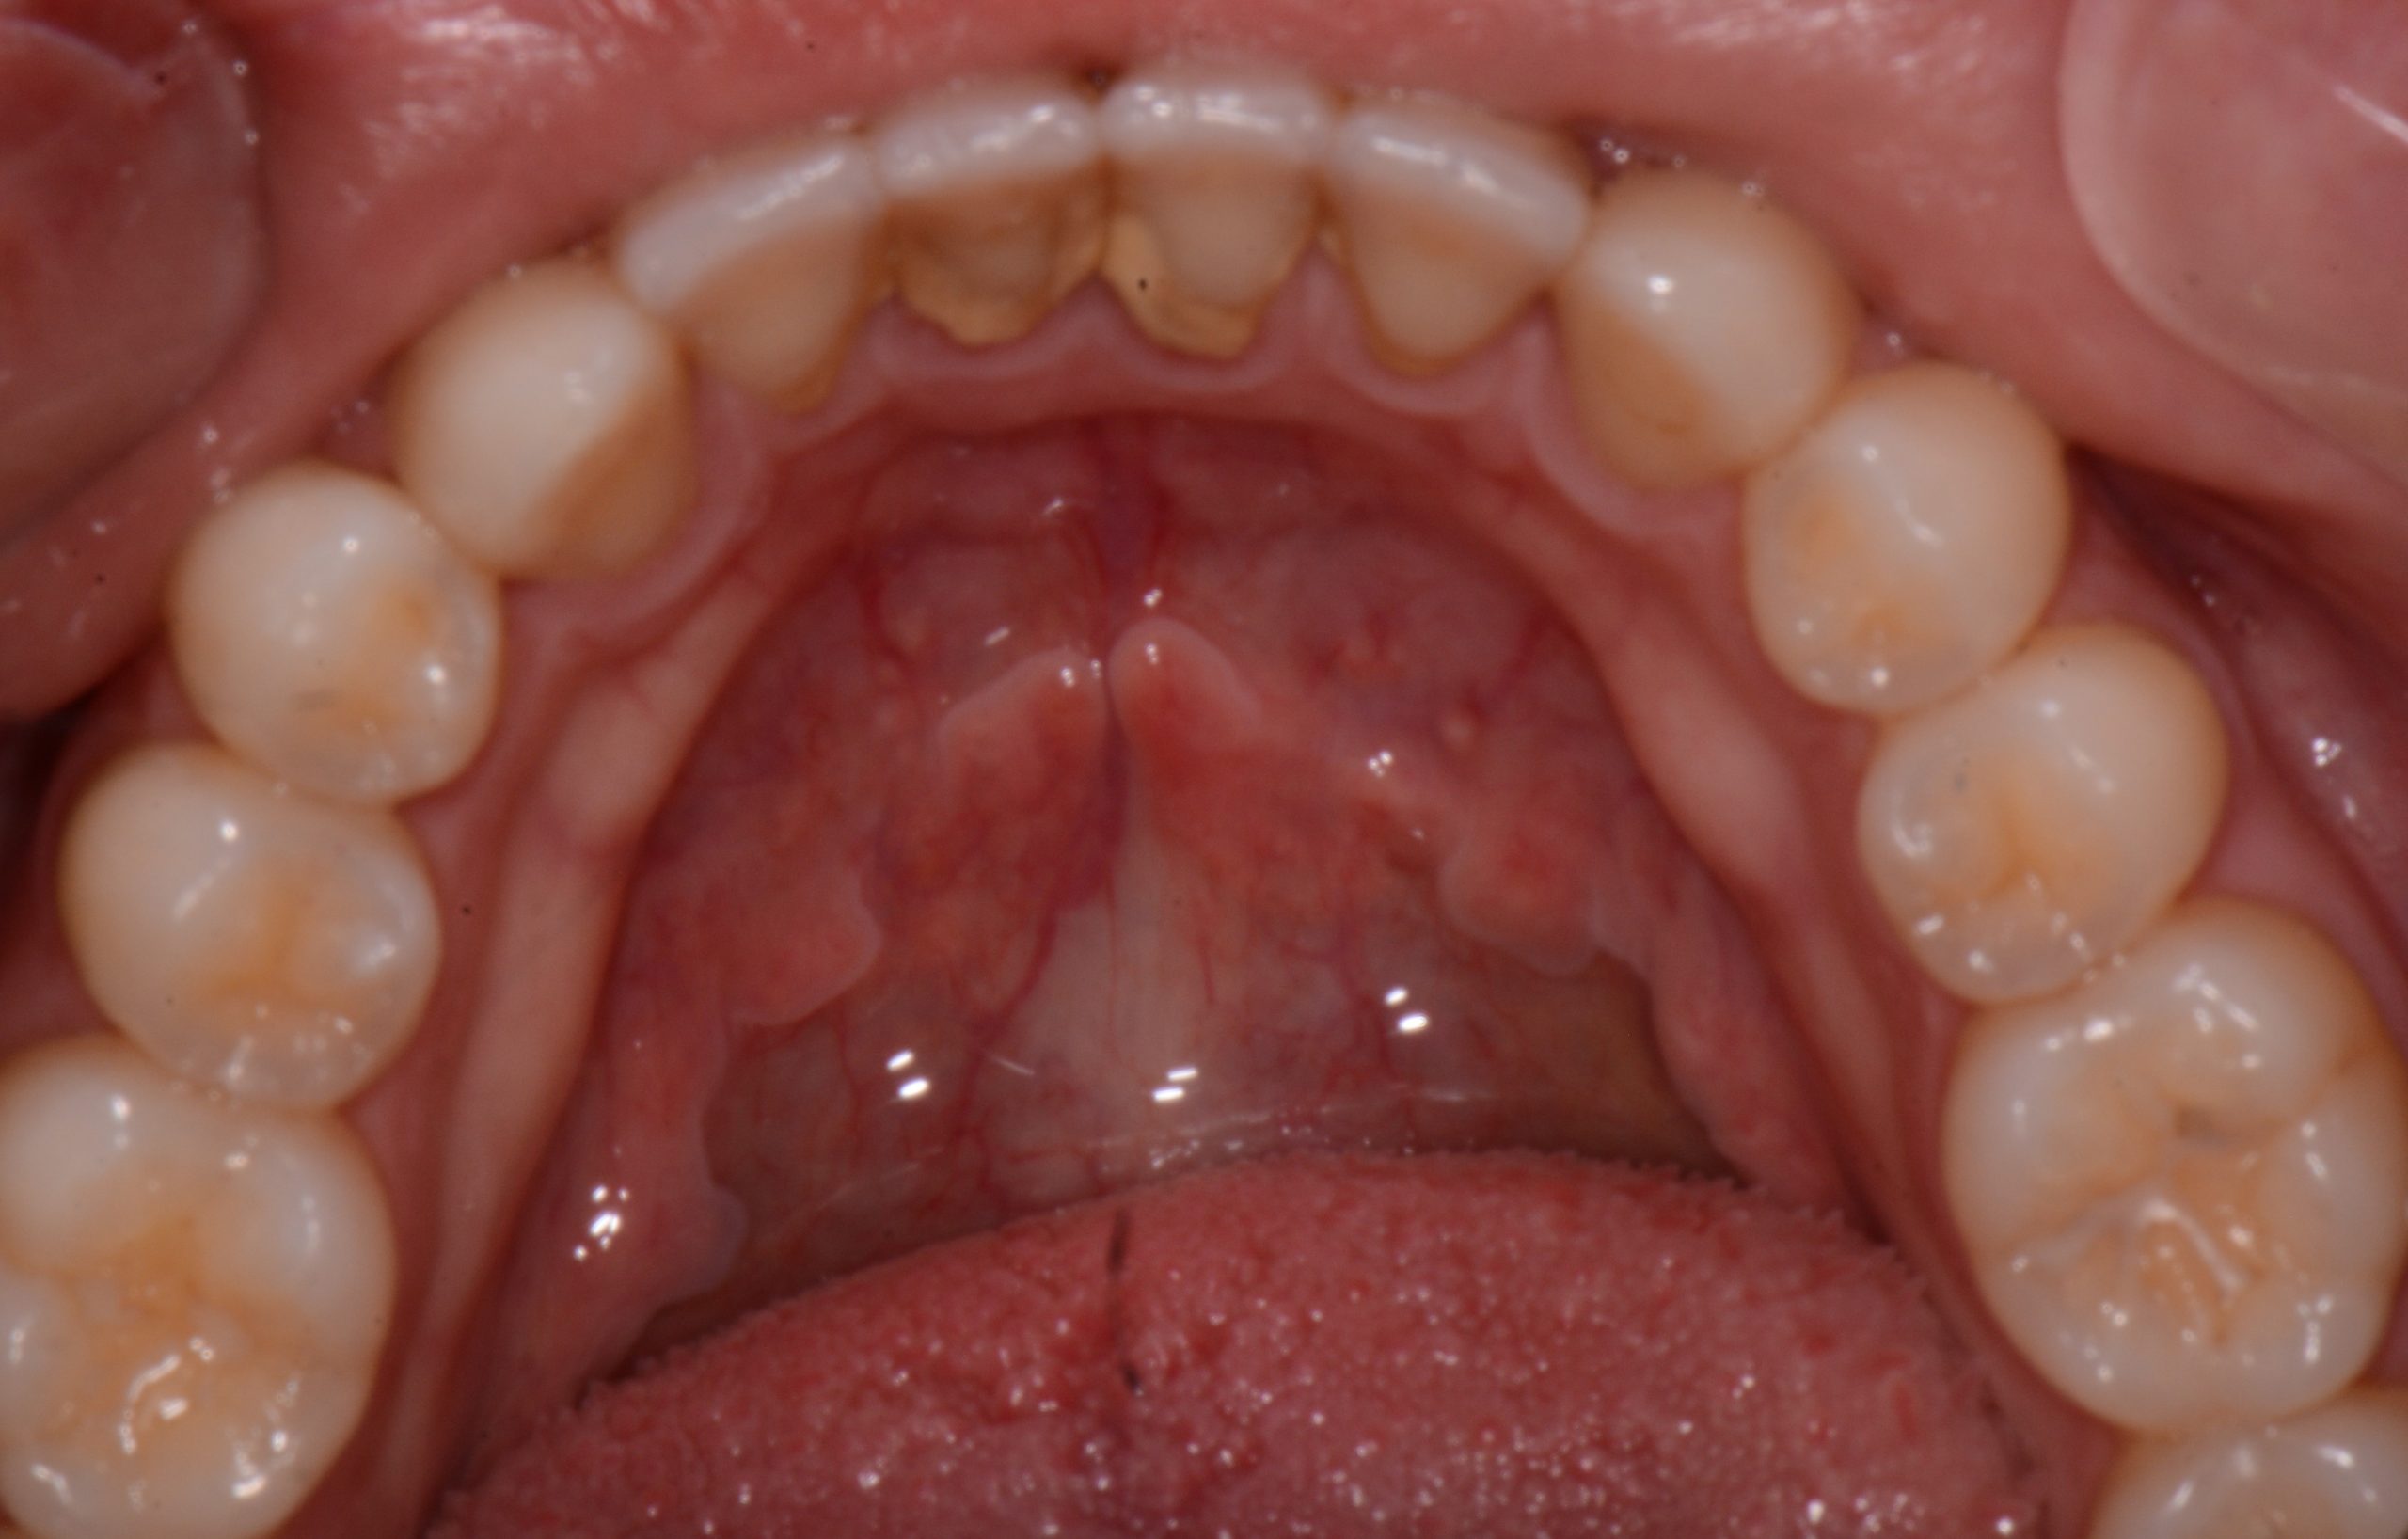

Gum disease is a common yet often overlooked problem that affects millions. If left untreated, it can lead to serious oral health issues and even tooth loss. Fortunately, there's a highly effective solution: Scaling and Root Planing. This non-surgical periodontal treatment is considered the gold standard for combating gum disease. At Seattle Dental Care, we […]